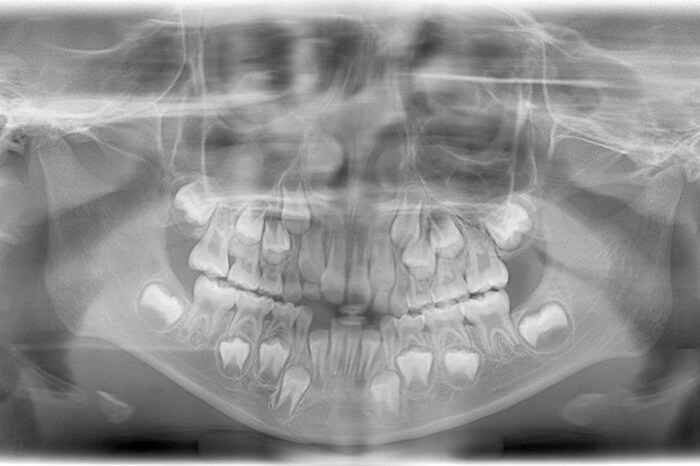

定期検診は、むし歯があるかないかを診るだけではありません。当院では、成長に合わせた様々な項目(むし歯、歯肉炎、磨き残し、乳歯から永久歯への生え変わりが正常にすすんでいるか、歯並びやかみ合わせ、「食べる・飲み込む・話す・呼吸する」が正しくできているか、生活習慣等)の確認を行い、クリーニング、ブラッシング指導、フッ化物塗布をおこないます。さらに、必要に応じて、レントゲンを撮影し(4~6歳ごろに、永久歯の数や位置、過剰歯の有無などをチェックします)、年齢、成長、状態に応じた適切な指導、処置を行っていきます。